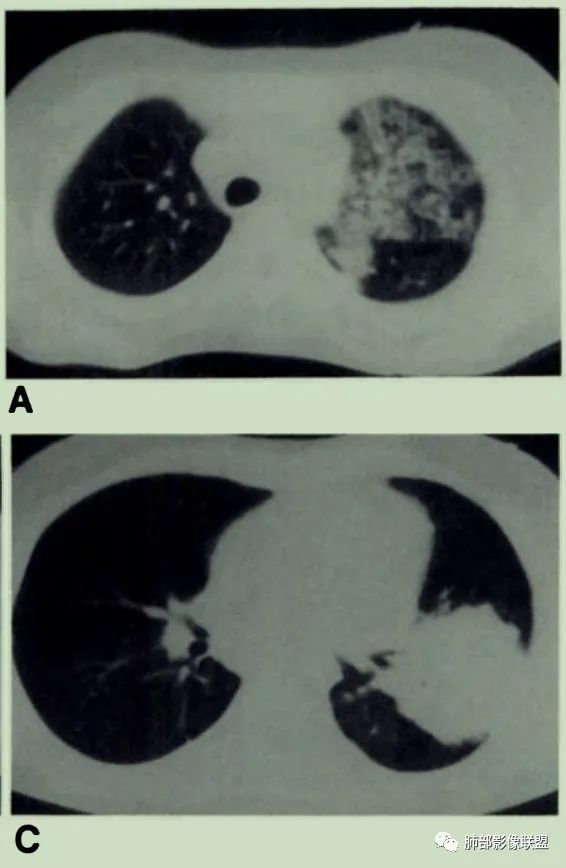

抗感染无好转的空气支气管征要警惕肺淋巴瘤。

或表现为网格状阴影,少数不典型的患者表现为弥漫性磨玻璃阴影。

有时候诊断不容易,可酷似肺炎!

或酷似肺癌!

①低度恶性的病变可以浸润肺间质但不破坏支气管结构。

②恶性程度较高、生长较快的病变可出现中心液化坏死、空洞。